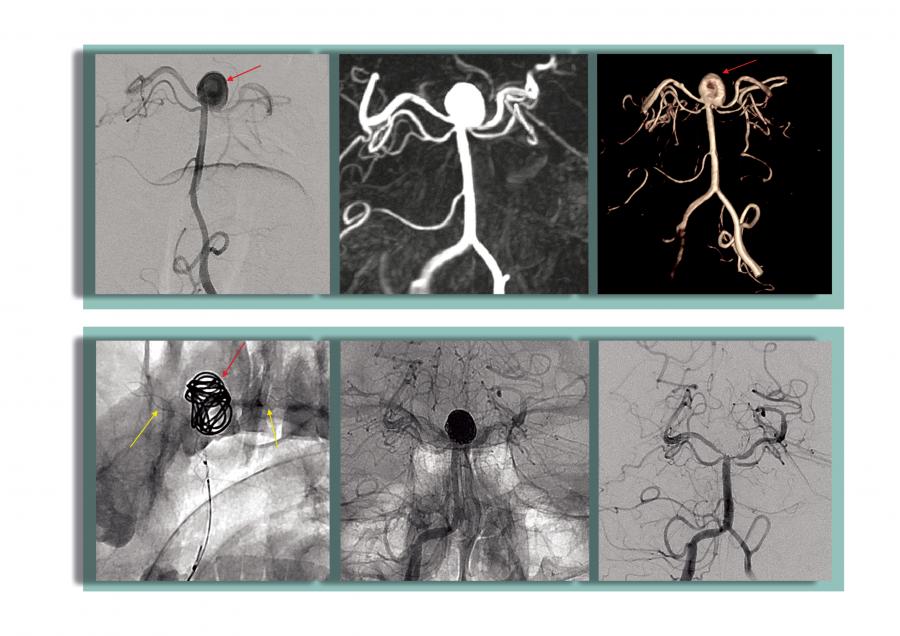

48 yaşındaki diğer hastamızın ilk incelemelerinde beyin kanaması bulgularına rastlandı. Çekilen Beyin Damarları Anjiyografisinde, 8 mm çapında baloncuk (anevrizma) tespit edildi. Patlaması an meselesi olan anevrizmaya kapalı yöntemle kasık atar damarından girildi. Sağ ve sol arka beyin damarını korumak için stent yerleştirildi. Bu aşamadan sonra kritik olan anevrizma koil (tel yumak) ile kapatıldı. Zorlu geçen bu girişimsel işlemler, hastamızın büyük ve riskli bir ameliyata gerek kalmadan şikayetlerini ortadan kaldırıp kısa bir sürede şifa ile taburcu olmasını sağladı.